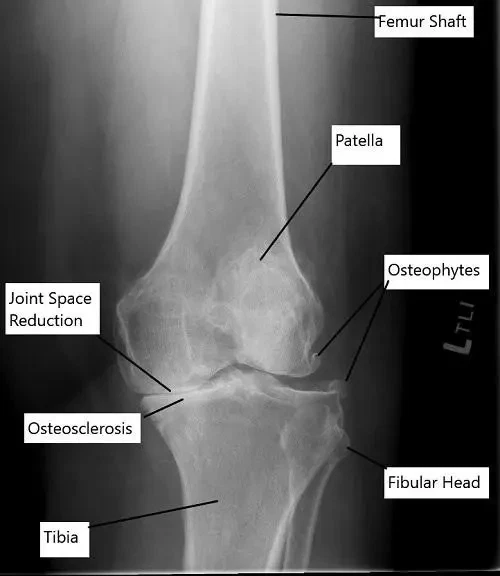

X-ray showing osteoarthritis of the knee.

How Doctors Find the Problem? (Diagnosis and Imaging)

A diagnosis is made through a physical exam, review of symptoms, and imaging studies. X-rays are most often used to look for joint space narrowing or bone changes seen in arthritis.